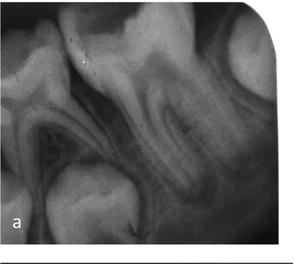

दुधाच्या दाढा पडून त्यांच्या जागी उपदाढा किंवा छोट्या दाढा येतात. मात्र वयाच्या सहाव्या वर्षी पहिली पक्की दाढ आणि बाराव्या वर्षी दुसरी पक्की दाढ येते ;सर्व दुधाच्या दाढांच्या मागे… अलीकडच्या दुधाच्या दाढा जर अजून पडायच्या असतील तर एक्स-रे मध्ये त्याखाली येण्यासाठी तयार असलेली पक्की दाढ सुद्धा दिसते पण पक्क्या दाढेच्या खाली अशी कुठलीच दाढ नसते; हे आम्ही दाखवतो .